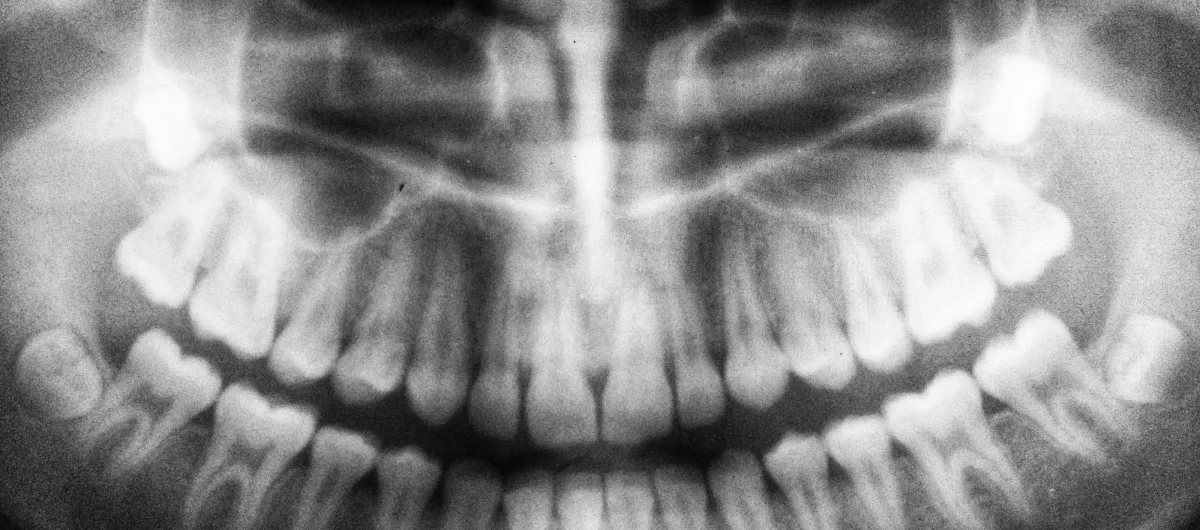

Black and white panoramic dental X-ray showing full adult teeth and jaw structure

Digital X-Rays

We use low-radiation imaging that delivers crystal-clear pictures in seconds. We can spot what needs attention and walk you through it together. You don't have to deal with the old-school wait or mess of film.

What are the benefits of digital X-rays over traditional ones?

Digital X-rays offer faster image capture with significantly less radiation exposure than traditional film. They're more comfortable and provide high-resolution images almost instantly. We can diagnose problems earlier and plan treatment more effectively. Plus, they're better for the environment since they don't require film or chemicals.